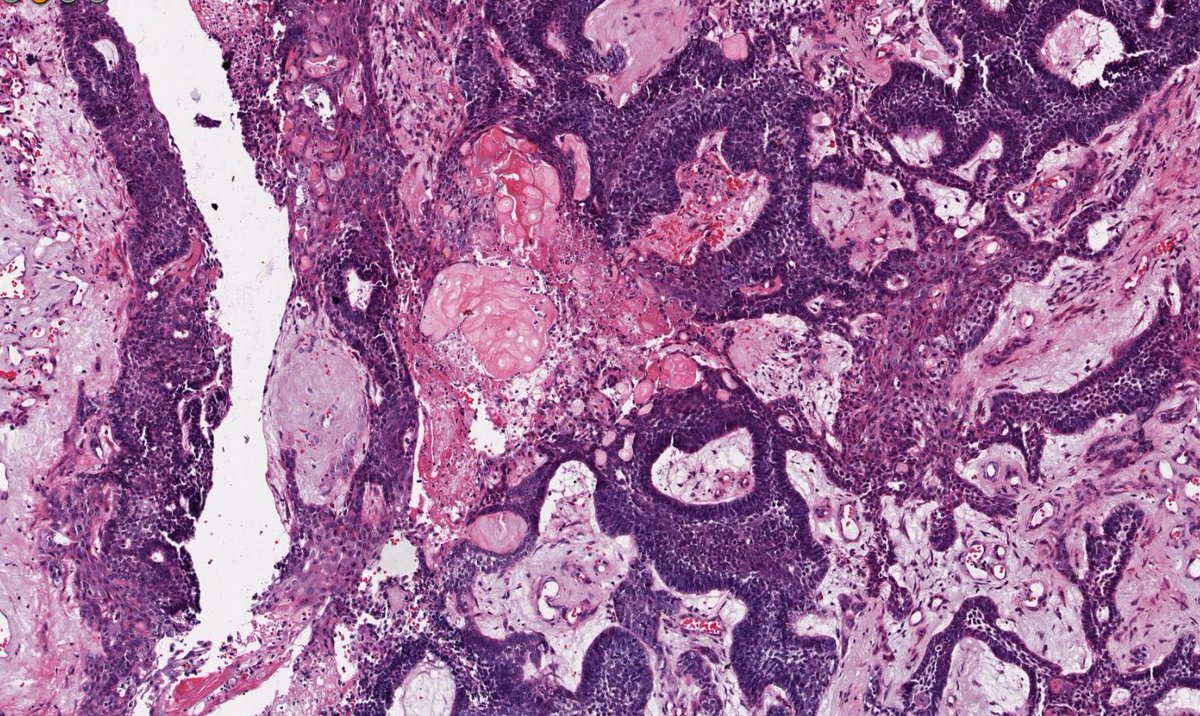

Miruna Popescu, MD

Miruna Popescu, MD@MirunaPopescu13·

Ulcerated mass in the colon. ▶️Geographic necrosis ▶️Lots of mitoses & apoptotic bodies ▶️Sheet-like & trabecular growth ▶️Highly atypical nuclei w/ prominent nucleoli ▶️Eosinophilic cytoplasm Based on 🔬H&E morphology, what is your diagnosis? #PathTwitter #GIPath

Miruna Popescu, MD tweet mediaMiruna Popescu, MD tweet mediaMiruna Popescu, MD tweet mediaMiruna Popescu, MD tweet media